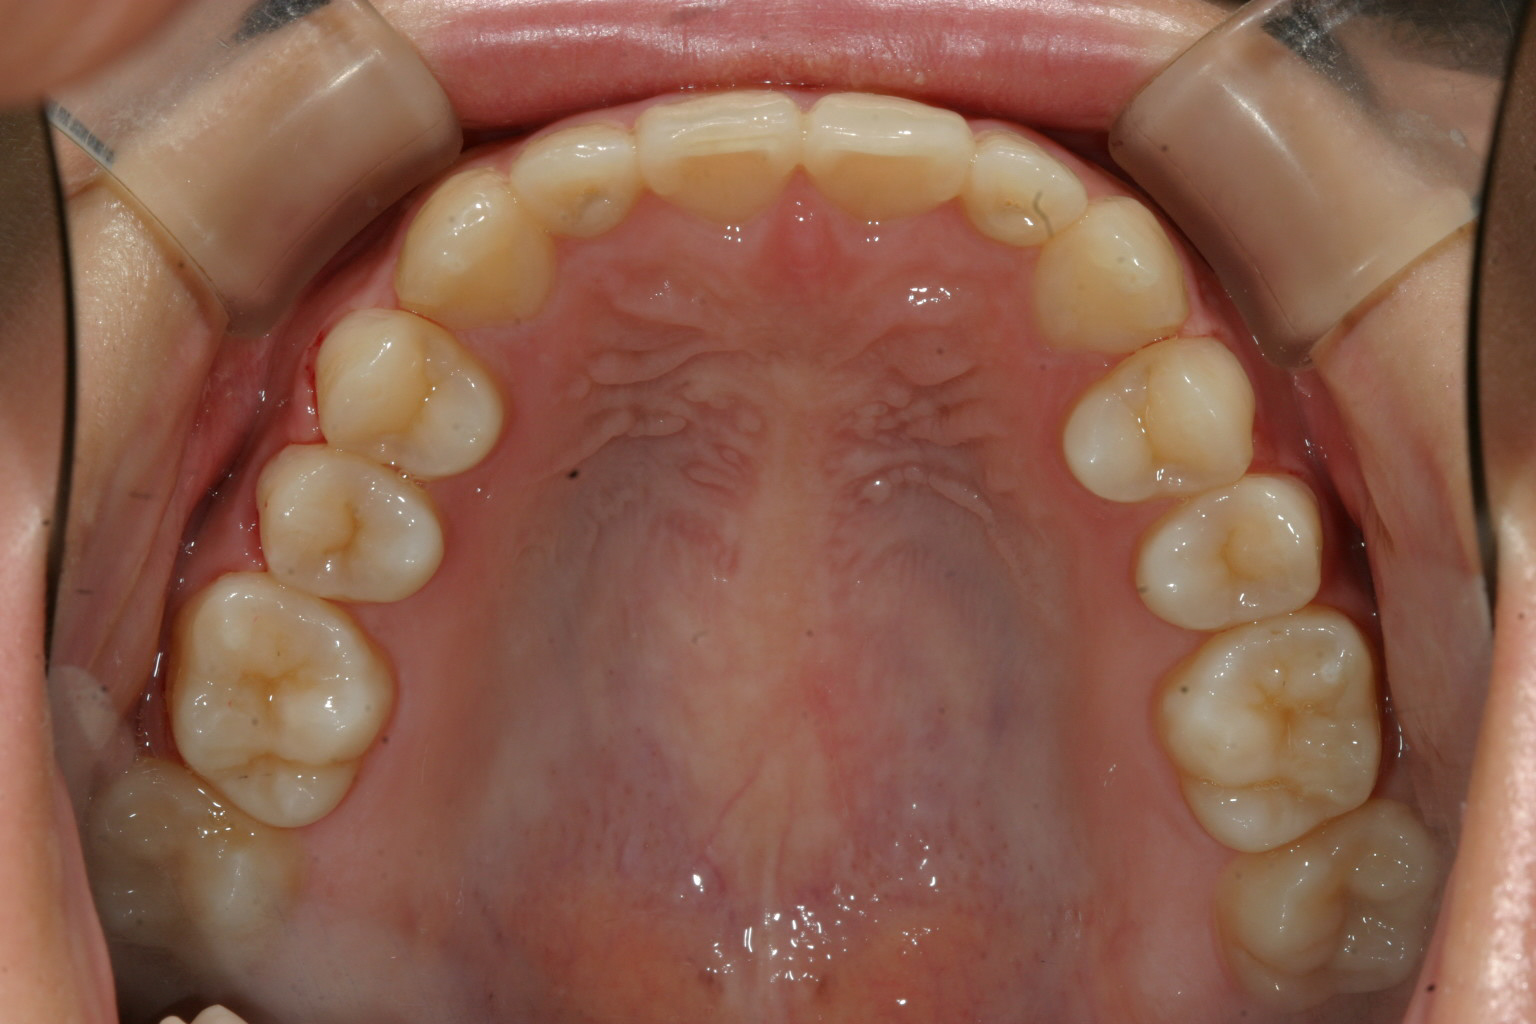

上の歯並びを綺麗なアーチにする為に前歯を出しました。

上を先に出して下の前歯も綺麗に並べました。

綺麗なオーバーバイトに改善しました。